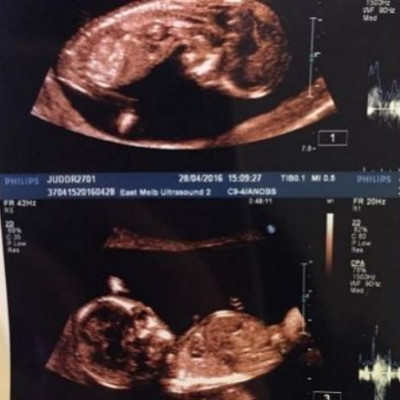

Διάσημο ζευγάρι: «Βρίσκομαι στην 20η εβδομάδα και επιτέλους το νιώθω να κλωτσάει!»